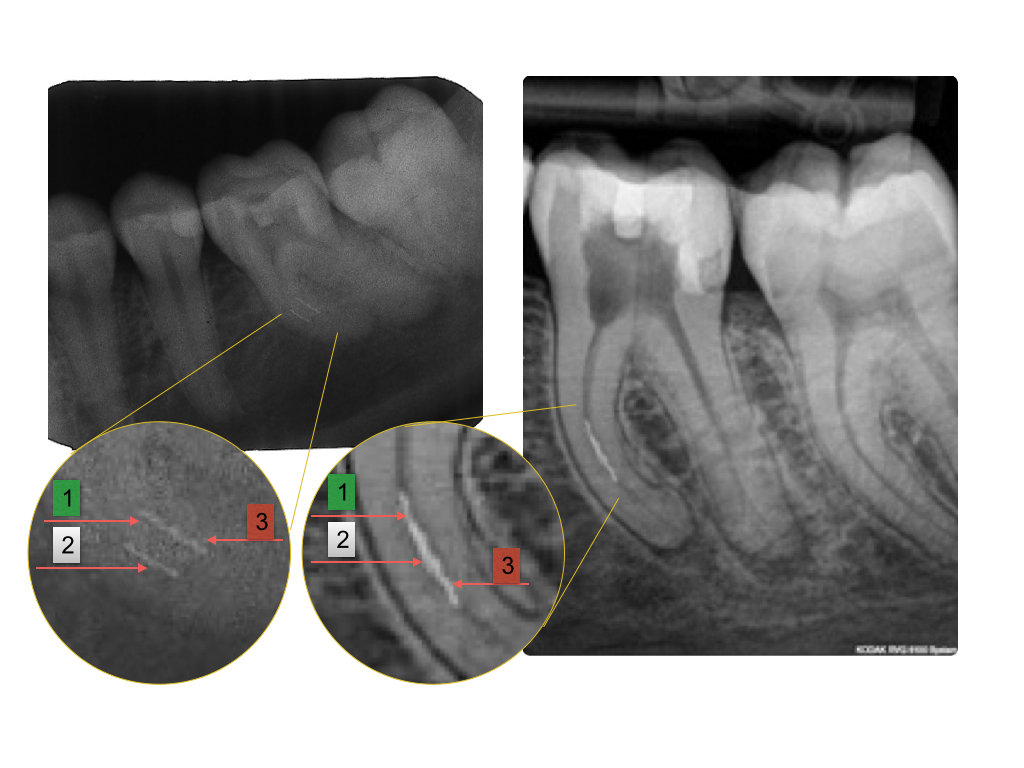

Instrumentenfrakturen (1)